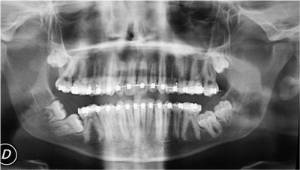

Es una especialidad odontológica que se dedica a la prevención, el diagnostico y el tratamiento de la patología (enfermedades, anomalías y lesiones) de los dientes, de la boca, de los maxilares y de las zonas anexas, que deben tratarse mediante técnicas quirúrgicas. Se trata de problemas que no pueden corregirse sólo con tratamientos conservadores (medicamentos, rehabilitación, etc.) y que deben solucionarse con maniobras quirúrgicas es decir con operaciones que tiene que realizar un dentista especializado en Cirugía Bucal.

Existen muchos tipos de patologías y técnicas que se incluyen en esta especialidad, pero destacaremos algunas de las más importantes y frecuentes:

- Cirugía implantológica (colocación de implantes en los maxilares).

- Cirugía sinusal (elevación del seno maxilar, etc.).